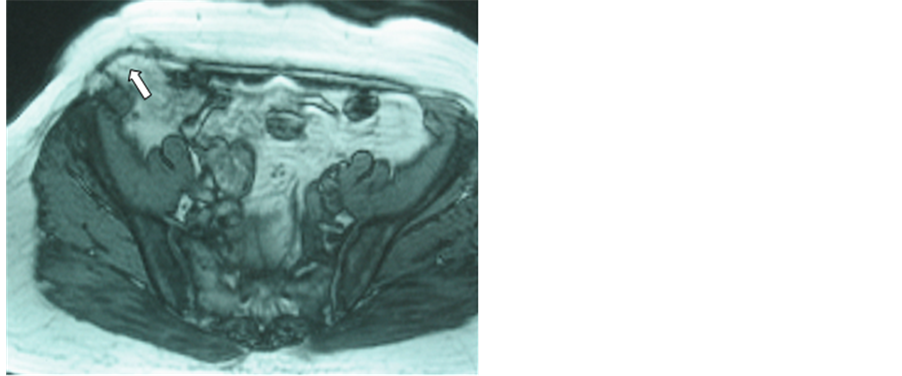

The three and six months control showed the evolution of the seroma, the integration of the mesh and the possibility of occult relapsing (Figure 5 and Figure 6), giving a complete information of the abdominal wall.

Regarding the late complications, a patient developed an occult relapse (Figure 5 and Figure 6), resolved by a new laparoscopic procedure.

Figure 5. A six month postoperative axial MRI control after laparoscopic surgery for a large umbilical and right-side incisional hernia. In this view the arrow shows the mesh with evidence of a relapse.

Figure 6. The same case of the Figure 5, in the sagittal view was possible to show perfectly an occult relapse in the right supra-iliac area.